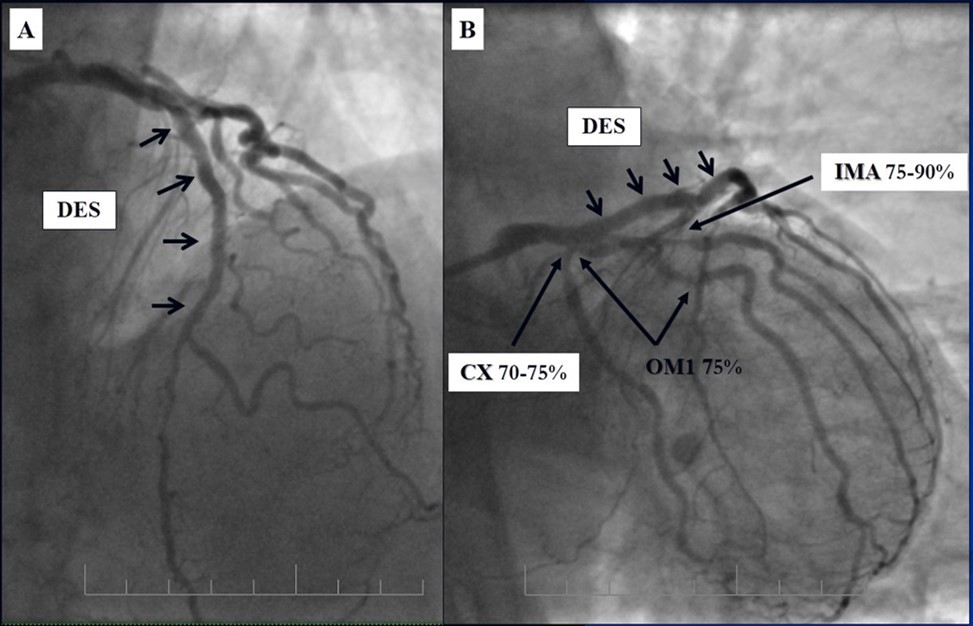

Angiography revealed rare anatomical variation LMCA quadrifurcation (Figure 1, Figure 2), 50% stenosis of the distal part of the LMCA, 40% stenosis of the ostial segment of left anterior descending (LAD) artery and diffuse prolonged 70-75-95% stenosis in mid-segment (Figure 3), 75% stenosis of the ostial segment of the circumflex (CX) artery, 75% stenosis of the ostial segment of the first marginal branch (OM1), 75-90% stenosis of the proximal segment of the intermediate artery (IMA), prolonged diffuse severe 90-95% stenosis of mid-segment of the right coronary artery (RCA) (Figure 4).

Figure 4.A - 50% stenosis of the distal segment of the LMCA; B - 70-75-95% stenosis in mid-segment of the LAD.

Due to financial problems the second stage was performed after 3 months (during this time the patient solved his financial problems). CAG revealed patent stents in LAD (Figure 7), and 60-70% restenosis by BMS in RCA (Figure 8). In-stent restenosis was treated by plain old balloon angioplasty (POBA), the optimal result was obtained (Figure 9). After LMCA quadrifurcation balloon predilation, 2.5×26 mm DES (Resolute Integrity, Medtronic) was implanted in the IMA, using a modified balloon mini-crush technique. The stent was minimally protruded in the LMCA and its edge was crushed by preloaded MB balloon. Next 2.5×30 mm DES (Resolute Integrity, Medtronic) was implanted in OM1 through the CX (first marginal and circumflex arteries in this particular case have the same ostium). The stent was protruded in the LMCA as in conventional modified balloon crush stenting technique, after stent deployment, its balloon was pulled back and overinflated, then protruded stent was crushed by preloaded MB balloon (Figure 10). 3.5×15 mm DES was implanted in the LMCA so that distal part of the stent covered ostial and proximal segments of the LAD. Sequential post-dilatations were performed using a kissing balloon technique (1. LMCA-LAD-IMA,2. LMCA-LAD-CX-1OM). After post-dilatations, through the stent implanted in CX-OM1, coronary wire and smaller diameter balloon (2.0 mm) were advanced in direction of the CX mid-segment and by balloon dilatation stent’s strut was opened (provisional stenting technique for CX). Finally, the proximal optimization technique was performed in the LMCA using a 3.5 mm diameter non-compliant balloon (Figure 11). The final angiographic image was good, the intervention ended without complications (Figure 11, Figure 12). We could not confirm the result with IVUS or OCT due to several technical and financial problems (not covered by insurance). 1 month after PCI, at regular checkout, the ejection fraction was 48%, the functional class of the Congestive Heart Failure decreased from class II-III to class I and the patient complaints have been disappeared.

Figure 10.Stenting of the LMCA quadrifurcation: A, B - balloon modified mini crush stenting of the IMA, C - angiography result, D,E - modified balloon crush stenting of the CX-OM1, F - angiography result.

Figure 11.Stenting of the LMCA quadrifurcation: A, B – Stenting of the LMCA; C –Kissing balloon post dilatation of the IMA-LMCA-LAD; D - Kissing balloon post dilatation of the CX-OM1-LMCA; E, F - angiography result.